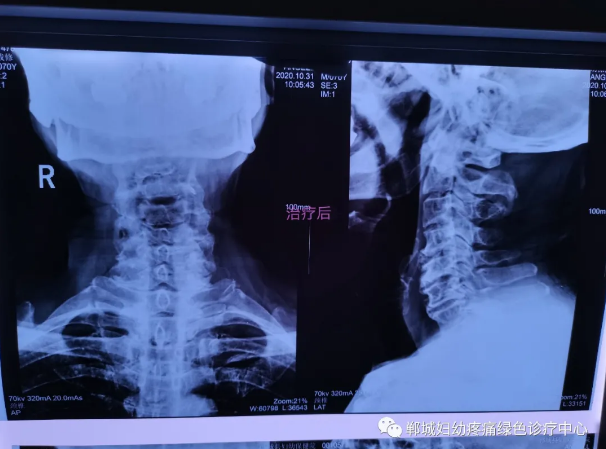

外星艙治療前

治療前李老師頸椎X線檢查影像

外星艙治療后

1個(gè)療程治療后頸椎X線檢查對(duì)比